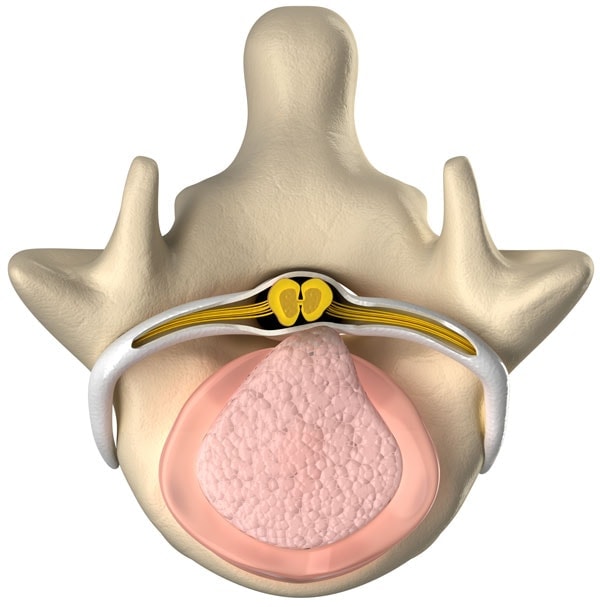

A bulging disc is also called a disc protrusion or bulge. This means that the outer covering of the disc (annulus) is partially torn or damaged and the inner gel is causing the area to bulge. This can put pressure on a spinal nerve and cause numbness and tingling (sciatica).

A herniated disc is also called a disc extrusion, slipped disc, sequestration, or “HNP” (Herniated Nucleus Pulposis). This means that the outer covering of the disc (annulus) is completely torn or damaged and the inner gel squirts out. This can put pressure on a spinal nerve or cause severe swelling and lead to numbness and tingling (sciatica).

Treating Bulging and Herniated Discs

Platelet Lysate is often used in the treatment of Bulging and Herniated Discs. This very specialized Regenexx-developed procedure utilizes natural growth factors from the patient’s own blood platelets. Regenexx’s extensive experience in Platelet Lysate, Platelet-Rich Plasma, and Bone marrow Concentrate from the patient’s own body enables us to determine the best treatment options to address your source of pain.

Platelet Lysate Spinal procedures are administered with precise imaging guidance to target the specific areas needing treatment and may offer relief from lower back or neck pain, buttock, and leg pain, or numbness and tingling in the arms, hands, legs, or feet. It’s a highly specific, precise image-guided non-surgical treatment alternative for patients suffering from bulging discs and herniated cervical, thoracic, or lumbar disc-related problems, performed only by specially trained Regenexx Physicians.